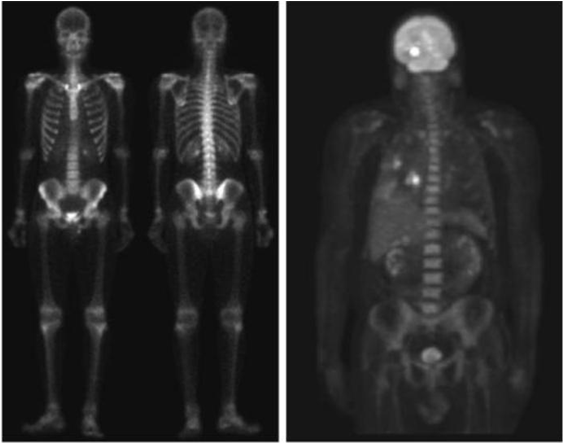

Gamma ray image

- 감마선의 투과성을 이용

- 주요 응용분야: 핵의학, 천문관측

a) 환자에게 감마선을 방사하는 방사선 동위원소를 주사, 감마 검출기로써 영상을 획득 - 병소의 위치 파악에 유용

b) PET(positron emission tomography) image